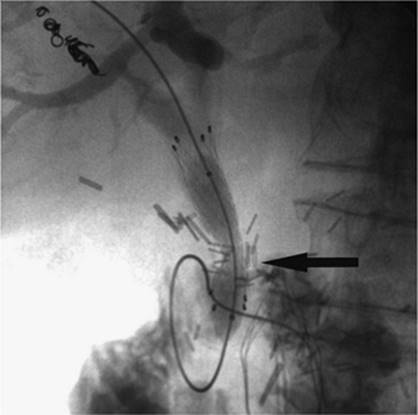

000280

Figure 35.21. Post–transjugular intrahepatic, portacaval shunting (TIPS) angiogram shows a patent TIPS shunt with a covered stent (black arrow). (Image courtesy of Harry K. Meisenbach, MD.)

Transjugular intrahepatic portacaval shunting (TIPS) was first conceived of and performed in dogs in 1969 by Josef Rosch et al. (36). The first human case of percutaneous TIPS was reported in 1988 (37). It is an effective nonsurgical and nonendoscopic means to control variceal bleeding by decompressing the portal venous system (38). A CT scan, ultrasound, or MRI is recommended to evaluate for patency of the portal vein as well as exclude hepatic neoplasm and evaluate for other anatomic considerations. The usual laboratory studies to check for hematocrit and coagulopathy should also be performed. IV antibiotics should be administered prior to the procedure. The technique consists of a percutaneous approach, usually ultrasound-guided canalization of the right internal jugular vein. From this approach, access is gained to the hepatic veins and pressure measurements are made from the portal vein using a wedged technique to the right atrium. A hepatic venogram is performed, followed by angiogram of the portal vein, using carbon dioxide and either a wedged technique or puncture of the hepatic parenchyma through the jugular access. Passage of a long curved needle is then performed from a satisfactory location in the hepatic vein, usually the right hepatic vein, into the identified location in the intrahepatic portion of the portal vein or its branches. Direct pressure measurements are made using the transjugular pathway (Fig. 35.20). If acceptable, balloon angioplasty of the intrahepatic tract between the hepatic vein and the portal vein is then performed. A stent, usually covered, is deployed from the portal vein to the hepatic vein through the tract to keep it patent and prevent hepatic recoil and restenosis (Fig. 35.21). Repeat pressure measurements are performed to confirm satisfactory pressures have been reached. Any additional adjustments that need to be made to the stent can be performed at this time, as well as embolization of varices if indicated.